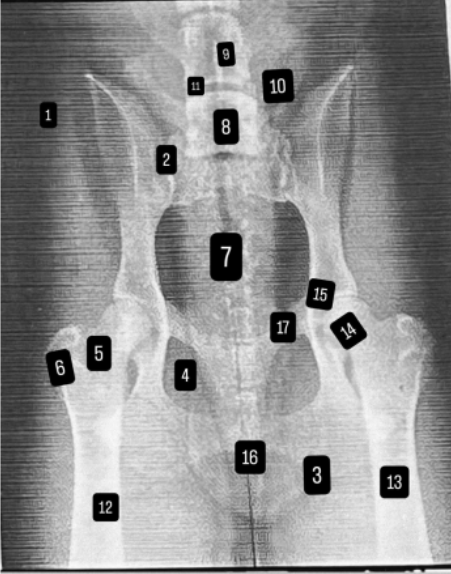

podaj numerki od 1-17

czym jest dysplazja stawu biodrowego

Dysplazja stawu biodrowego to wrodzona (lub rozwijająca się w młodym wieku) wada budowy stawu biodrowego, polegająca na jego nieprawidłowym dopasowaniu.

W prawidłowym stawie głowa kości udowej dobrze „pasuje” do panewki miednicy i porusza się w niej stabilnie. W dysplazji panewka jest zbyt płytka lub głowa kości udowej ma nieprawidłowy kształt, przez co staw jest niestabilny i dochodzi do jego nadmiernego luzu.